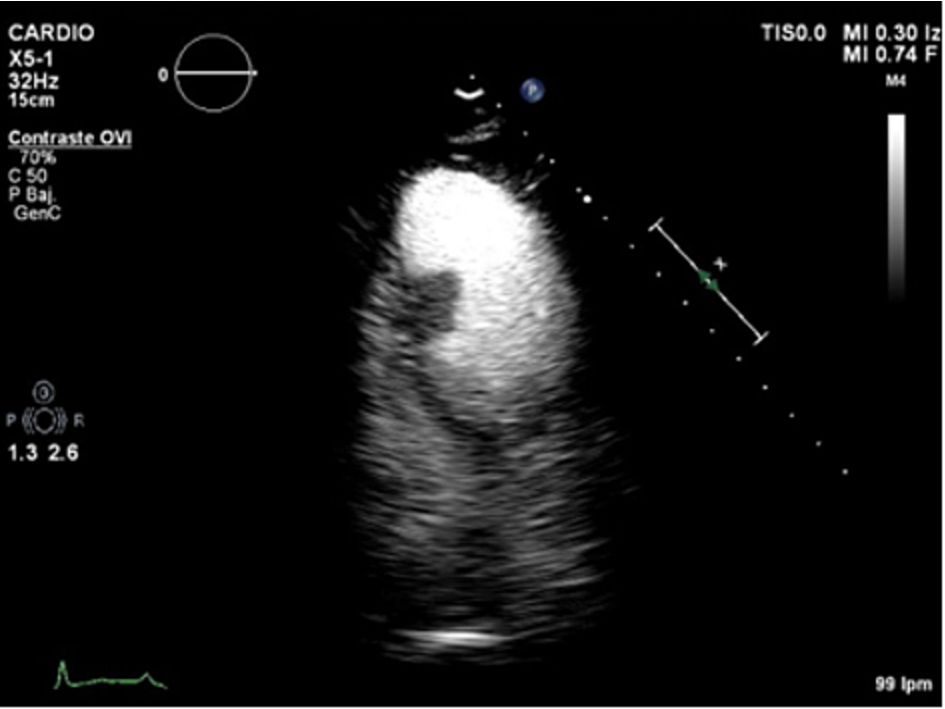

Echo-contrast was administered, showing perfusion of the mass, excluding the diagnosis of thrombus.

Conventional transthoracic echocardiography was repeated a week later, without changes. 2D-echocardiographic study was completed with intravenous echocardiographic contrast to demonstrate perfusion of the mass, excluding the diagnosis of thrombus (Movie II in the Data supplement) and with 3D echocardiography for better visualization and establishing spatial relationships of the mass (Movie III and Movie IV in the data supplement).